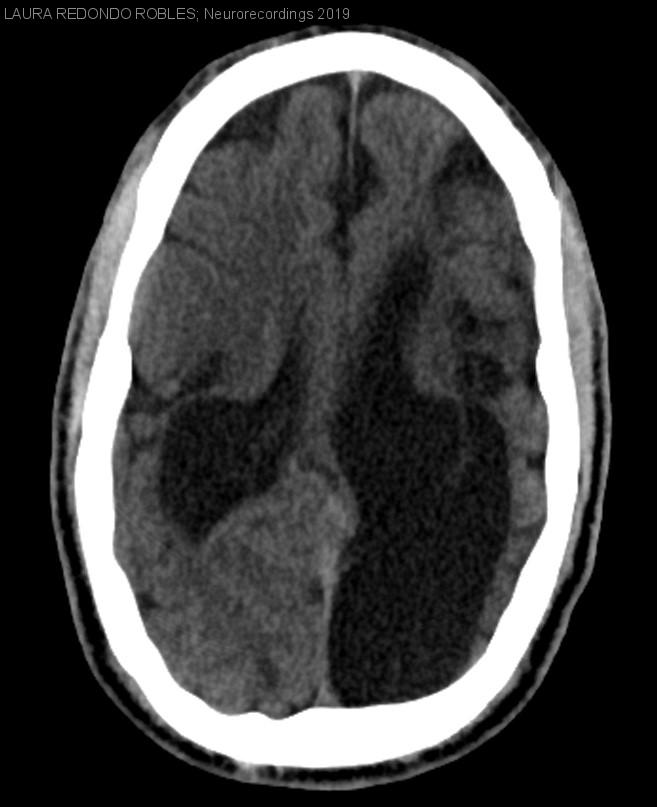

Hidrocefalia ex vacuo

Diagnóstico final: Hidrocefalia ex vacuo

Paciente de 32 años con antecedente de encefalopatía connatal con retraso mental moderado que presentó su primera crisis epiléptica tónico-clónica en julio de 2017; por este motivo se le realizó una TAC craneal que demostró...